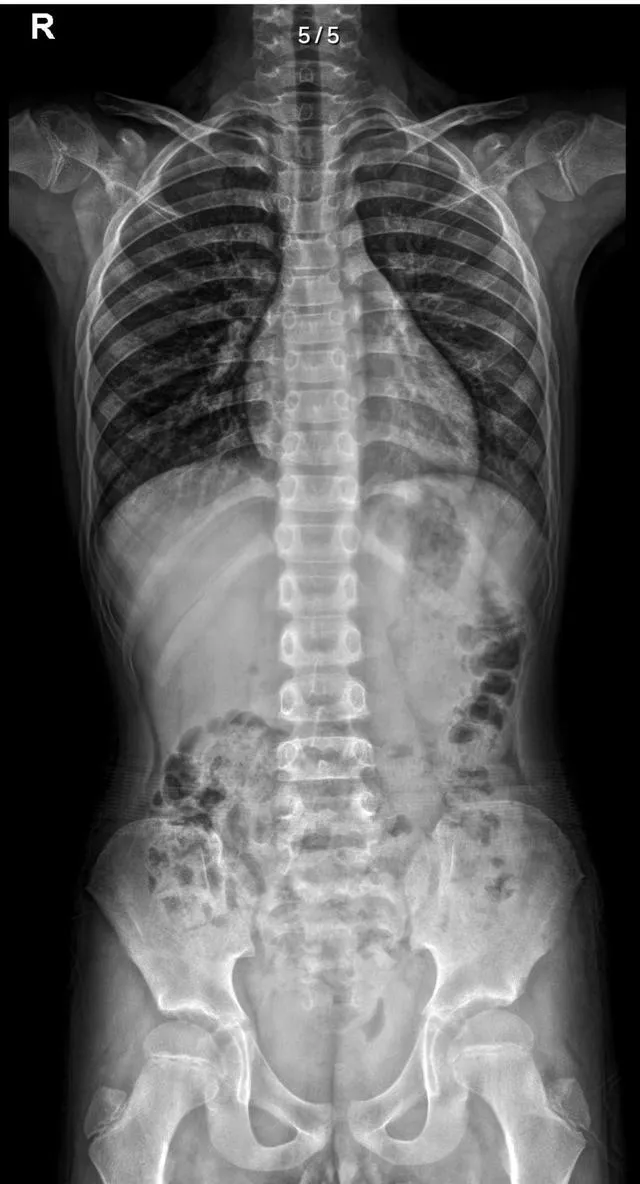

治療前,文同學的脊柱整體中線明顯向右側偏移。經過專業的治療與康復訓練後,文同學的脊柱整體中線回歸,體態得到了改善。

1、體格檢查: 右腰隆起ATR:2°,中線右偏,臀稍左移。

2、影像檢查: 脊柱整體向右側偏移,兩側髂骨左高右低,兩側股骨左高右低。